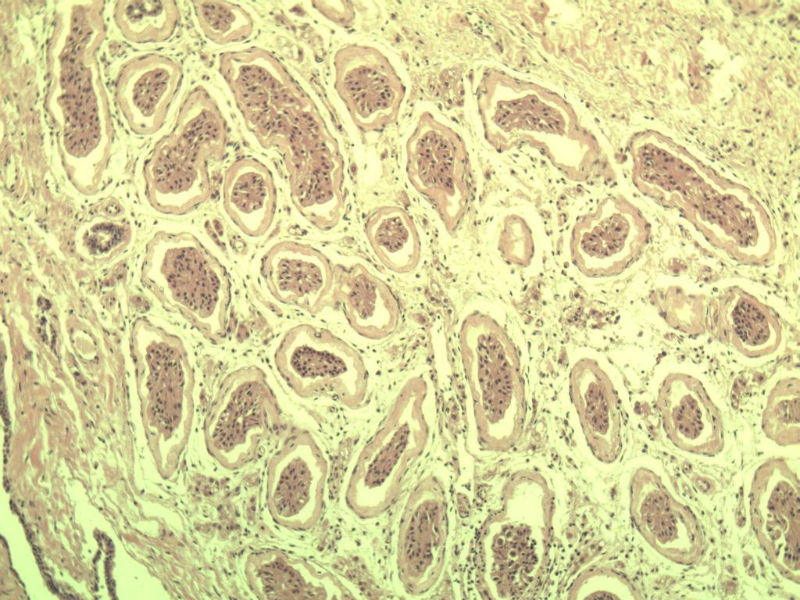

男 27岁 腹腔隐睾 5*3*2 cm, 切面灰红灰黄、实性、质中,请各位老师看看,是精原细胞瘤吗?感觉不像.